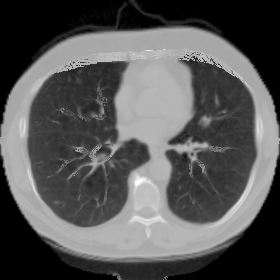

We then test our method on slices of chest CT images obtained from the Open Access Biomedical Image Search Engine [2]. Fig. 10(a) and 10(b) show the source image and target image respectively, and the intensity difference is shown in Fig. 10(c). The registration result obtained by our proposed method is shown in Fig. 10(d) (see also the result with the deformed underlying grid in Fig. 10(e)). From the final intensity difference plot in Fig. 10(f), it is easily to see that our method matches not only the two large components but also the small dot at the center very well. On the contrary, DDemons [47] produces a suboptimal registration result with a significantly larger mismatch of the small component at the center (see Fig. 10(g) and Fig. 10(h)).